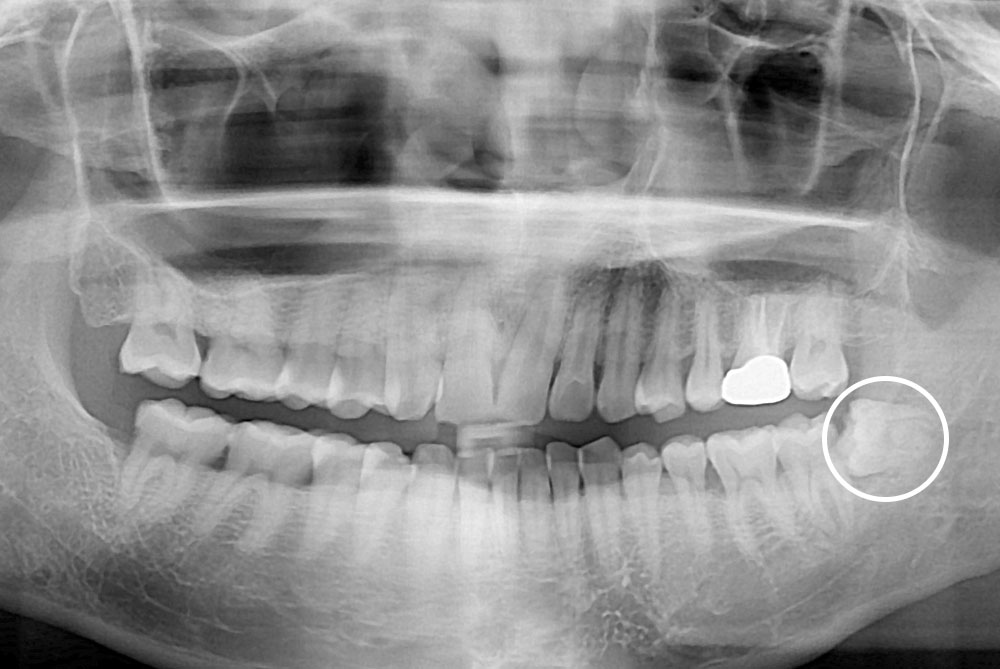

[사랑니] 매복 사랑니 발치

치료후 : 2019-09-27

세종치과는 구강악안면외과학 박사이신 원장님이 발치하는 치과입니다.